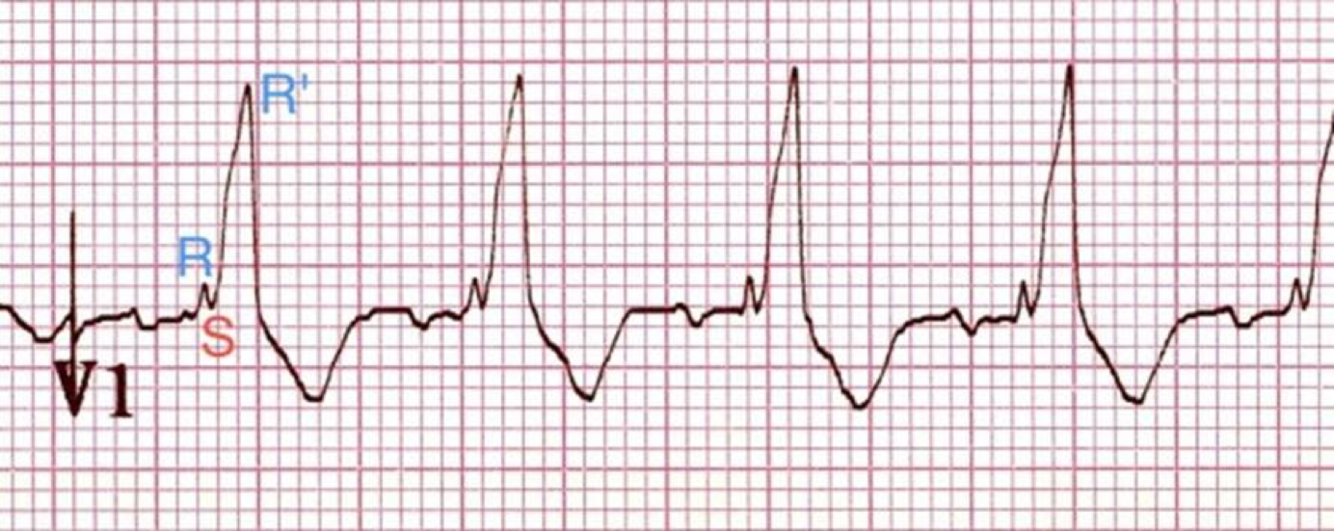

Identify this arrhythmia

RBBB, R & R’, sharp peaks in V1-2